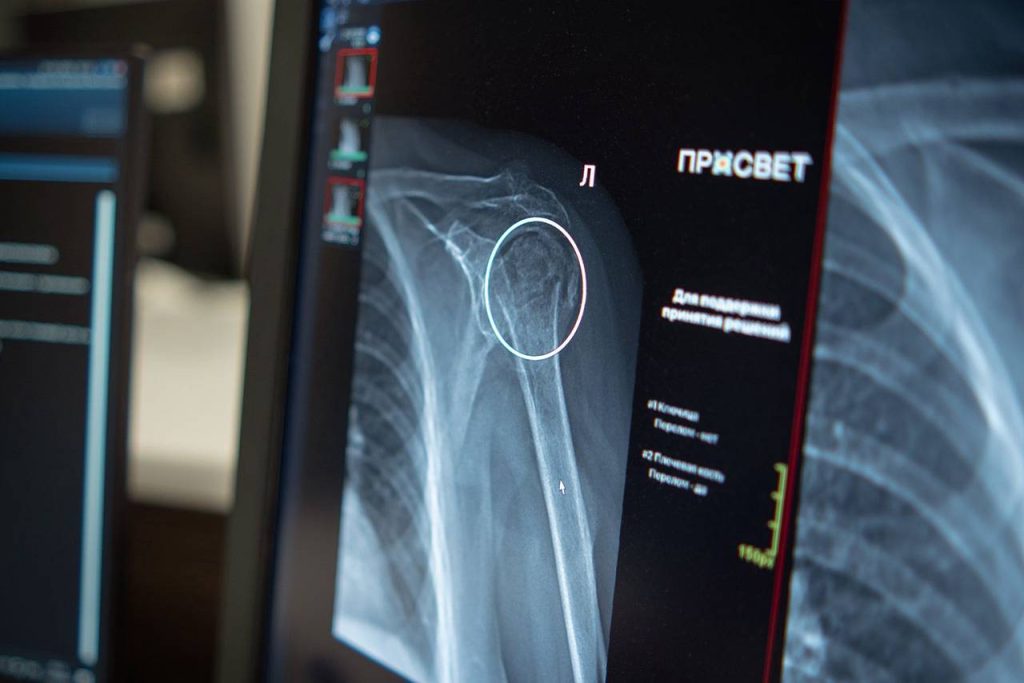

Он добавил, что в Москве активно внедряют ИИ в здравоохранение. Новая система помогает врачам выявлять переломы плечевого сустава на рентгеновских снимках. Алгоритм автоматически выделяет проблемные области и выполняет необходимые измерения, что ускоряет анализ снимков и повышает точность диагностики травм. Подобный сервис особенно важен в травматологических пунктах, где необходимы скорость и точность для своевременного назначения лечения и предотвращения осложнений.

Новый ИИ-сервис будет использоваться в городских больницах, поликлиниках и травмпунктах при диагностике переломов плеча. Для точной интерпретации рентгеновских снимков таких травм требуется особое внимание врача, сообщили на сайте мэра Москвы.